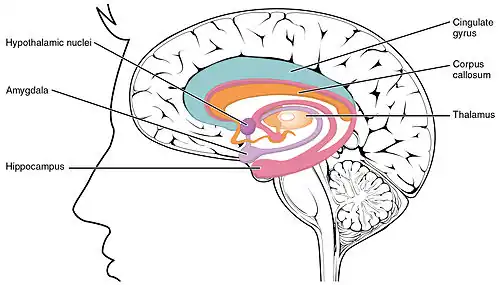

Location of important brain structures associated with LENAS. Note the thalamus and corpus callosum.

LENAS is seen with damage to the white matter and axons within the brain. The external human LENAS brain shows findings in several major structures. There is mild atrophy of the frontoparietal regions of the brain and a mild reduction of the thalamus and rostral (front) part of the caudate nucleus (which is located in an area of the brain called the basal ganglia).[5] Abnormalities in the frontal, frontoparietal, and temporal lobes are most severe and predominant with LENAS and asymmetry of the cerebral hemispheres has sometimes been found.[5] LENAS also may show moderately enlarged lateral ventricles and atrophy in corticospinal tracts as well as in the pons.[5]

The area where it is seen to be the most pronounced abnormalities appear in the white matter below the pre- and postcentral gyri that extend through the posterior limb of the internal capsule into pyramidal tracts of the brain stem.[5]

Specific Immunostains are used as the easiest identification of neuroaxonal spheroids in LENAS which appear as round to oval shaped swellings and are seen in affected white matter.[5] If there appears to be a large amount of loss in myelin sheaths on axons and these spheroids, LENAS progressed to become widespread.[5]